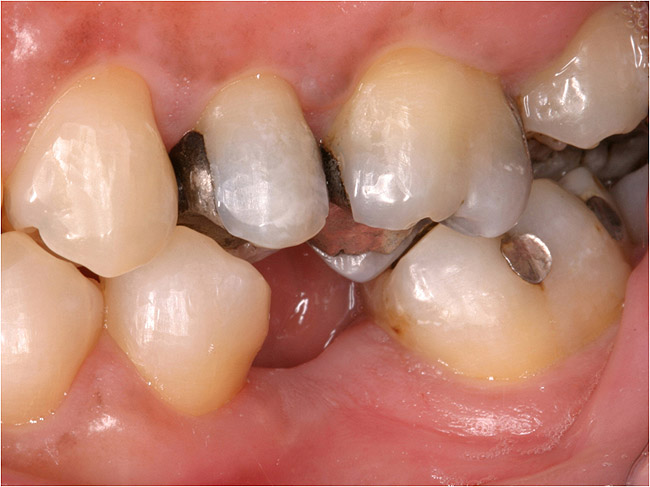

Figure 4a  Before treatment, missing lateral incisors replaced with failing conventional cantilever FPDs with canine abutments. Patient lacked inter-root space for implant therapy, denied orthodontic therapy, and chose revision FPD therapy.

Figure 4a

Figure 4b  Before treatment, missing lateral incisors replaced with failing conventional cantilever FPDs with canine abutments. Patient lacked inter-root space for implant therapy, denied orthodontic therapy, and chose revision FPD therapy.

Figure 4b

Figure 4c  Completed revised 2-unit porcelain-fused-to-gold cantilever FPDs, ovate pontic design, cemented with Maxcem Elite‚Ñ¢ (Kerr Corporation).

Figure 4c

Figure 4d  Completed revised 2-unit porcelain-fused-to-gold cantilever FPDs, ovate pontic design, cemented with Maxcem Elite‚Ñ¢ (Kerr Corporation)..

Figure 4d